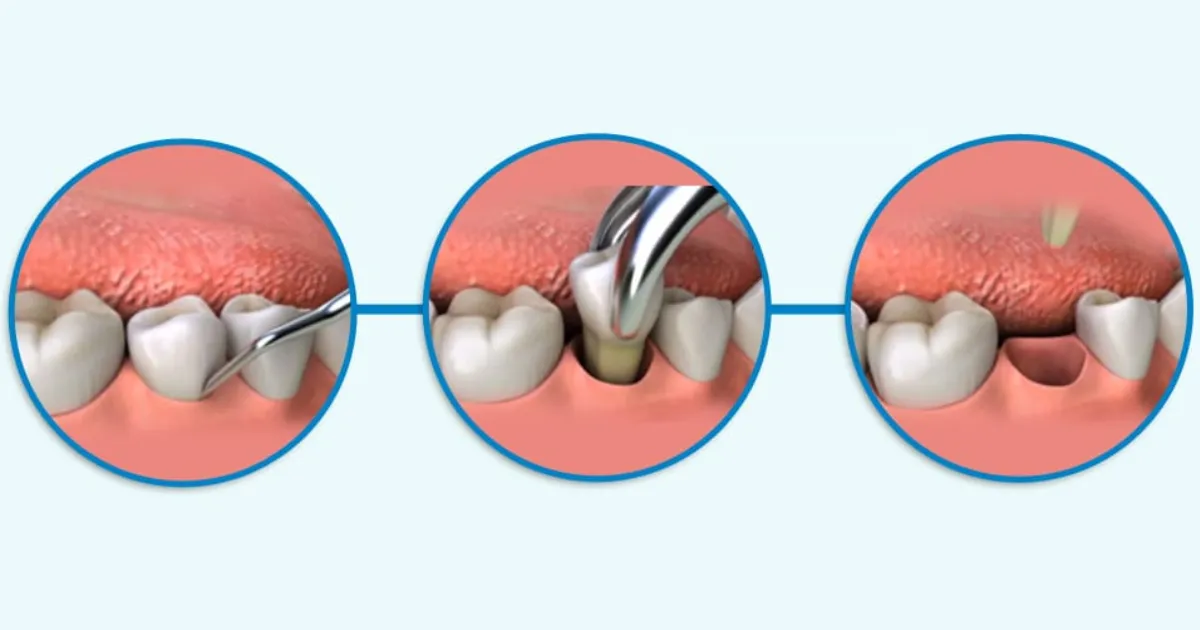

Quy trình nhổ răng chi tiết tại Nha khoa APEX

- Thực hiện nhổ răng: Bác sĩ sẽ sử dụng các dụng cụ nha khoa chuyên dụng (kìm, bẩy,…) để nhẹ nhàng lấy răng ra khỏi ổ răng. Kỹ thuật nhổ răng của bác sĩ APEX được thực hiện khéo léo, giảm thiểu tối đa xâm lấn, giúp vết thương nhanh lành.

- Xử lý sau nhổ răng: Sau khi nhổ răng, bác sĩ sẽ tiến hành cầm máu, làm sạch ổ răng, và khâu vết thương nếu cần thiết.